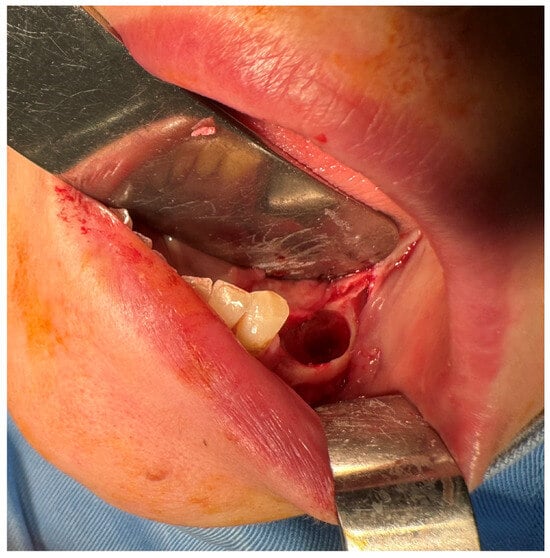

2.4. Second Surgical Intervention

2.5. Third Surgical Intervention